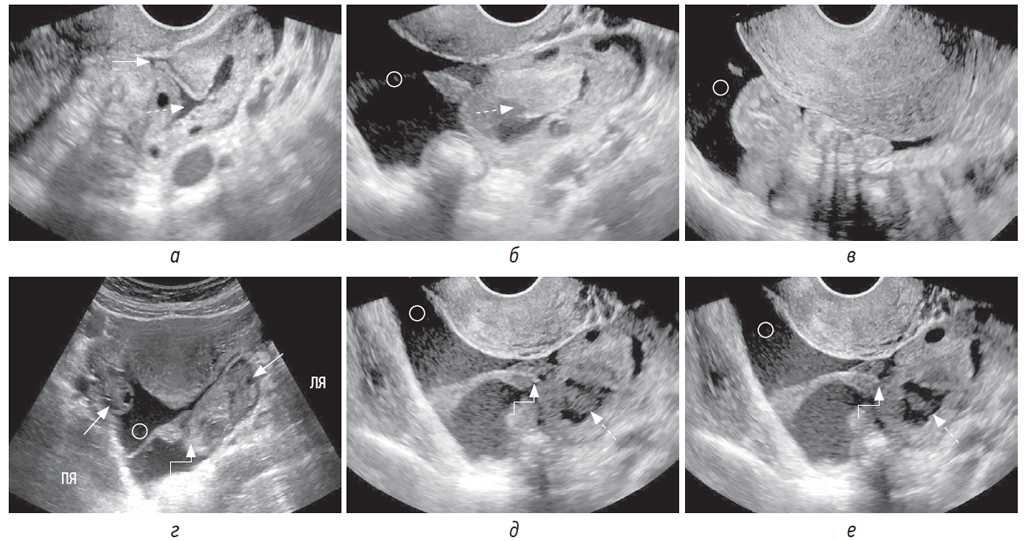

Ультразвуковая картина кистозного образования в яичнике зачастую разнообразна. Кистозное образование иногда бывает трудно определить из-за частичного или полного спадения полости либо из-за большого количества прилежащих тромботических масс (рис. 2, г–е) [9]. Кроме того, выявление геморрагической кисты значительно затрудняет полиморфизм сонографической картины: 1) мелкосетчатое и среднесетчатое строение средней эхогенности, в 2/3 случаев эти структуры занимают всю или большую часть кисты (рис. 1, д–з); 2) однородное содержимое в сочетании с множественными или единичными, тонкими, полными или неполными, неправильной формы перегородками; 3) в полости кисты сгустки крови в виде включений преимущественно высокой эхогенности, имеющие неправильную форму и пристеночную локализацию (рис. 3, г) [10].

Рис. 2. Пациентка 29 лет поступила с резкой болью в малом тазу, возникшей на фоне полового акта. При трансабдоминальном исследовании (а — аксиальная плоскость; б — сагиттальная плоскость) в полости малого таза определяется эхогенная кровь (круг) со сгустками (звездочка). При трансвагинальном исследовании (в, г) в полости малого таза в большом количестве определяется эхогенная кровь (круг) с наличием сгустков (звездочка), изоэхогенных геморрагической кисте желтого тела. На трансвагинальных сонограммах в В-режиме (д, е) и с использованием ЦДК (е) в яичнике определяется кистозное образование (пунктирная стрелка) с толстой и гиперваскулярной стенкой, с геморрагическим содержимым и наличием параовариально сгустков крови (звездочка). Стрелкой отмечена интактная (неповрежденная) ткань яичника

Рис. 3. Пациентка 27 лет поступила с болью в области малого таза. При трансвагинальном УЗИ (а, б) в левом яичнике определяется спавшаяся полость (а, пунктирная стрелка) неправильной формы с сомкнутым местом разрыва (стрелка), во время исследования полость (б, пунктирная стрелка) увеличилась в размерах за счет кровотечения и увеличилось количество несвернувшейся эхогенной крови (круг) в малом тазу. Трансвагинальная (в) и трансабдоминальная (г) сонограммы: эхогенная кровь в позадиматочном пространстве (круг). Увеличенный левый яичник с наличием полости с геморрагическим содержимым и сгустком, свисающим от места разрыва (г, уступ со стрелкой). На трансвагинальных (д, е) сонограммах: эхогенная кровь в позадиматочном пространстве (круг), увеличенный левый яичник с наличием полости с геморрагическим содержимым (пунктирная стрелка) и сгусток, начинающийся от места разрыва яичника (уступ со стрелкой)

Самой частой причиной разрыва яичника с гемоперитонеумом служит киста желтого тела, для которой при УЗИ характерна толстая стенка с зубчатыми краями. Применение цветового допплеровского картирования (ЦДК) существенно помогает не только в выявлении кисты на фоне тромботических масс, но и в дифференцировке кисты желтого тела от других образований на основании гиперваскуляризации по периферии и отсутствия цветовых сигналов во внутренних перегородках и структурах, представляющих собой организованные сгустки крови и нити фибрина (рис. 1, е; рис. 2, е) [10]. При трансабдоминальном УЗИ выявить спавшуюся кистозную полость практически невозможно, но при трансвагинальном/трансректальном исследовании допплеровские методики могут помочь в ее идентификации (рис. 3, а, б, г–е).

Место разрыва при УЗИ можно предположить на основании следующих признаков:

1) при крупных сгустках, окружающих травмированный яичник, из кистозной полости в параовариальное пространство распространяется ткань, изоэхогенная тромботическим массам; на этом уровне в месте предполагаемого разрыва определяется нарушение целостности капсулы яичника (рис. 1, л, м);

2) при минимально выраженном тромбозе непосредственно к месту предполагаемого разрыва прилежит сгусток, хорошо визуализируемый на фоне жидкой крови (рис. 3, б, г–е).